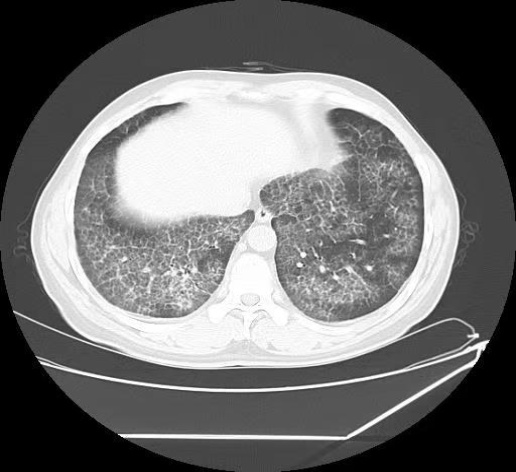

病例二:患者罗伟,男,37岁,矿业工人,因“胸闷、气短20天,加重伴右侧胸痛1天”入院。患者20天前出现活动后胸闷、气短,偶有咳嗽、咳痰,自行口服抗感染药物无效。入院后肺部CT显示双肺弥漫性斑片状磨玻璃密度增高影及网格影,双肺下叶微结节(部分钙化),考虑双肺间质性病变及PAP可能。支气管镜检见气管及支气管黏膜正常,右下叶外基底段亚支远端行支气管透壁活检。病理结果显示右肺下叶肺泡腔内粉染无定型物,PAS染色阳性,倾向PAP诊断。

入院评估与初步检查:① 入院后完善肺CT检查,结果显示双肺弥漫性斑片状磨玻璃密度增高影及网格影,双肺下叶微结节(部分钙化),考虑双肺间质性病变及PAP可能。② 行支气管镜检查:观察气管及支气管黏膜正常,管腔通畅。于右下叶外基底段亚支远端行支气管透壁活检,使用活检钳取肺组织4块,标本送检病理。③ 同时于右中叶外侧段行肺泡灌洗,使用生理盐水100 ml,回收60 ml灌洗液,留样送检。④ 病理诊断与特殊染色:肺组织病理检查显示右肺下叶肺泡腔内粉染无定型物。⑤ 特殊染色结果:PAS染色呈阳性,粘液卡红染色阴性,结合HE形态及临床表现,倾向诊断为PAP。